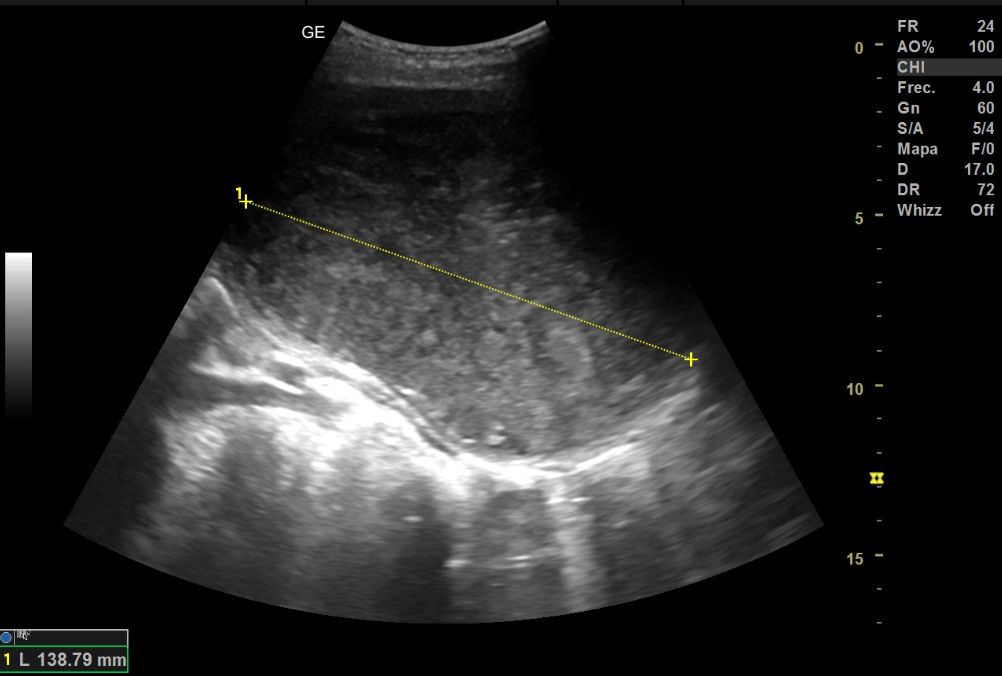

Se le realiza a la paciente ecografía abdominal con sonda cónvex, donde se objetiva en la zona anteriormente mencionada masa de unos 138 mm en su eje longitudinal y 108x90 mm en un corte transversal, no pudiendo precisar con exactitud el origen de la misma. Al aplicar el Doppler color se observa una captación periférica.